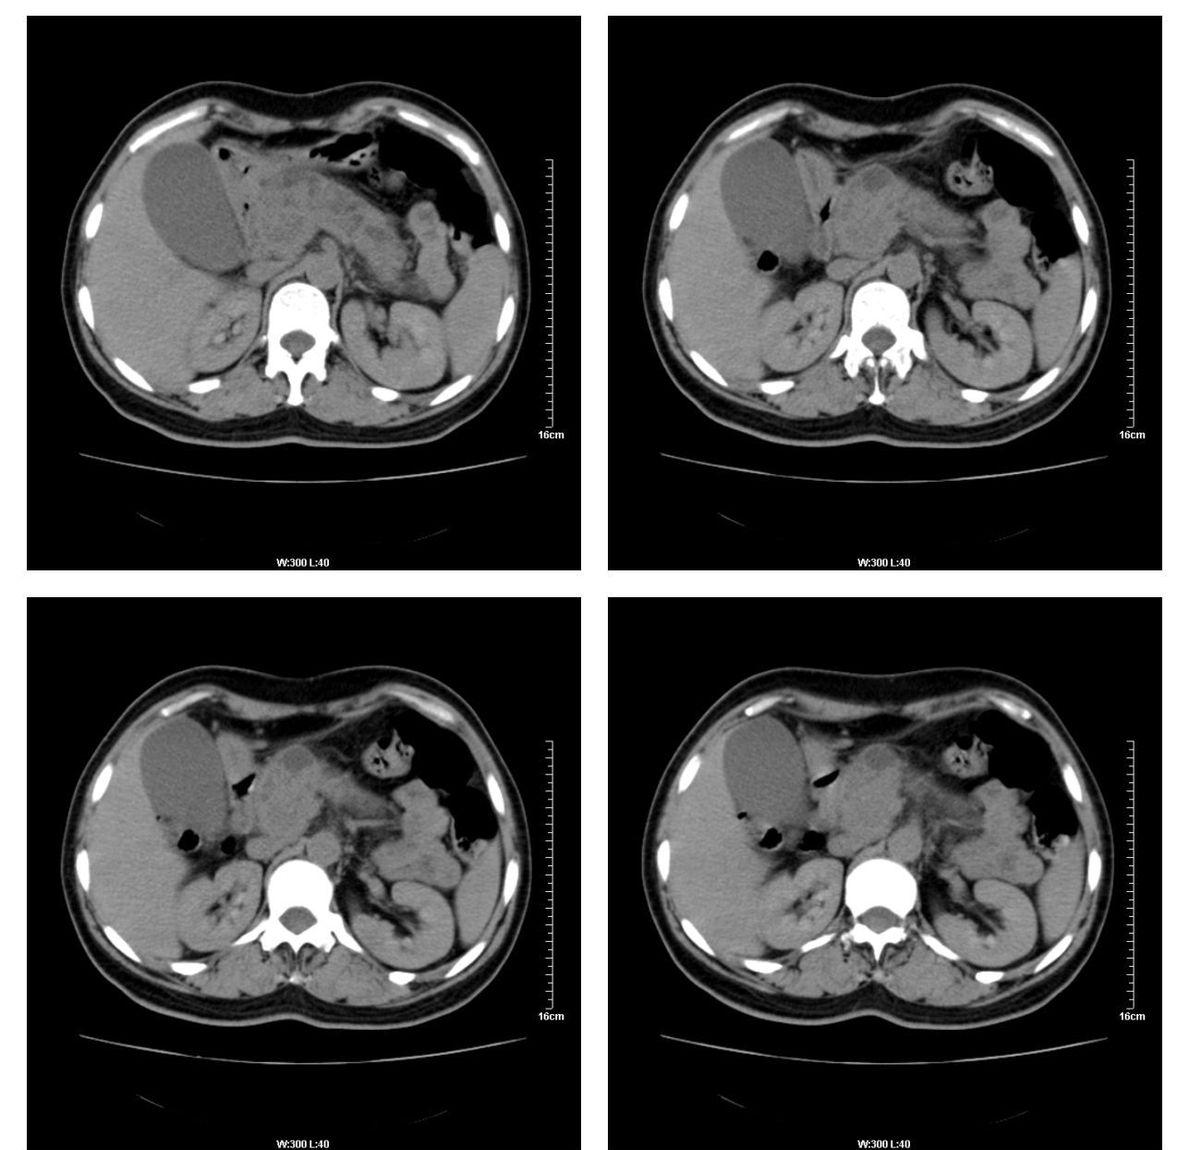

标题: CT13800:女性,52岁。腹痛、腹胀、消瘦及乏力5个月。 [打印本页]

标题: CT13800:女性,52岁。腹痛、腹胀、消瘦及乏力5个月。

慢性胰腺炎、胰腺假囊肿形成,胆总管梗阻,胆囊扩张

慢性胰腺炎、胰腺假囊肿形成。

慢性胰腺炎、胰腺假囊肿形成,胆总管梗阻,胆囊扩张,不除外胰腺占位

考虑慢性胰腺炎、胰腺假囊肿形成。

各期时间抓的不太好,门静脉始终显示不佳(门脉瘤栓形成?)。